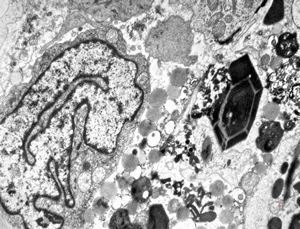

bone marrow - crystalloid inclusions Charcot-Leyden crystals formation

bone marrow - crystalloid inclusions Charcot-Leyden crystals formation v.s.